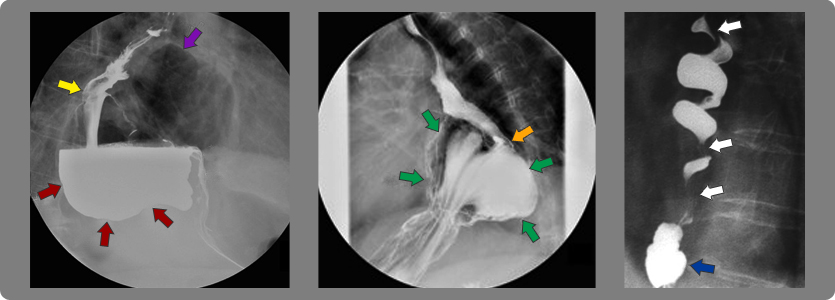

2- Estrechez (estenosis) del esófago

Cuando la esofagitis es grado C o D se producen múltiples cicatrizaciones de la pared y eso origina retracción de la misma con la consiguiente estrechez del esófago y dificultad para tragar (disfagia).

Flechas blancas: ondas terciarias de esófago

Flechas rojas: áreas de estrechez esofágica

Flecha azul: hernia hiatal

Hernia hiatal y ERGE

La hernia hiatal es una afección en la cual el estómago asciende desde la cavidad abdominal por debajo del diafragma hacia el mediastino (compartimiento central de la cavidad torácica) por arriba del diafragma. En la mayoría de los casos a menos que sea una hernia grande no produce síntomas per se y no necesita tratamiento, pero hasta en un 40% de los casos acompaña al ERGE, en cuyo caso se corrige con cirugía. Se dice que el ascenso del EEI desde su posición natural intraabdominal al tórax condiciona que este pierda su capacidad de funcionar como válvula y se facilite el ERGE.

Flecha amarilla: esófago

Flecha morada: estómago herniado lleno de aire

Flechas rojas: estómago herniado lleno de bario

Flecha naranja: unión esófago- gástrica

Flechas verdes: saco gástrico herniado

Flechas blancas: ondas terciarias del esófago